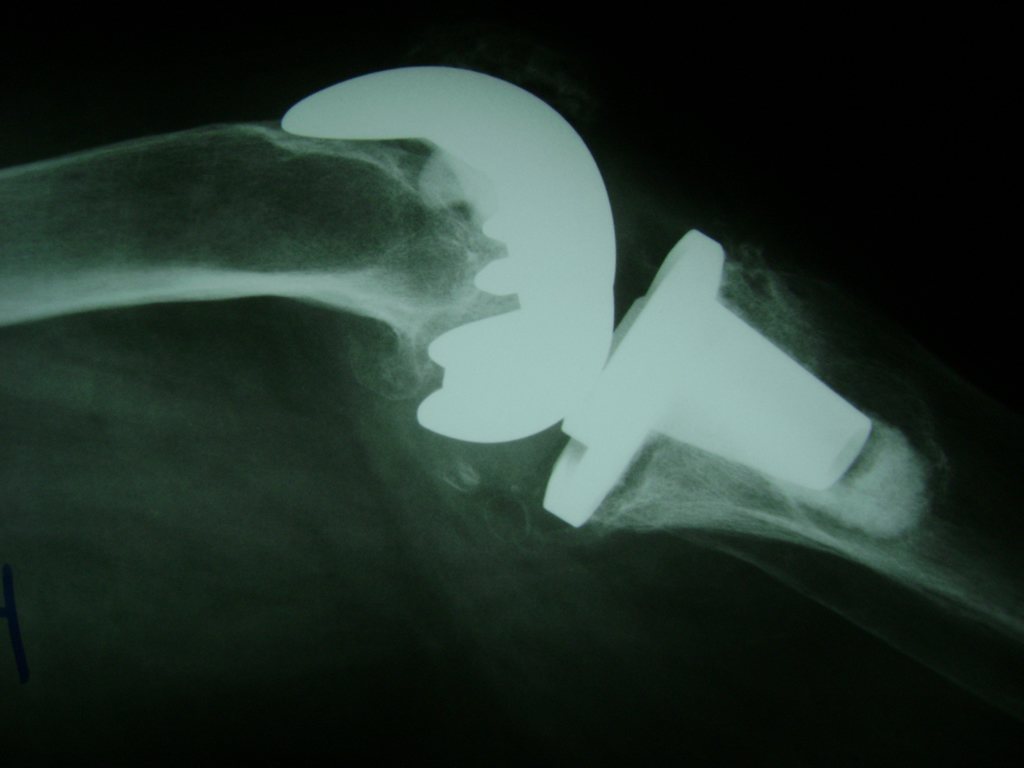

Húmero - Rodilla